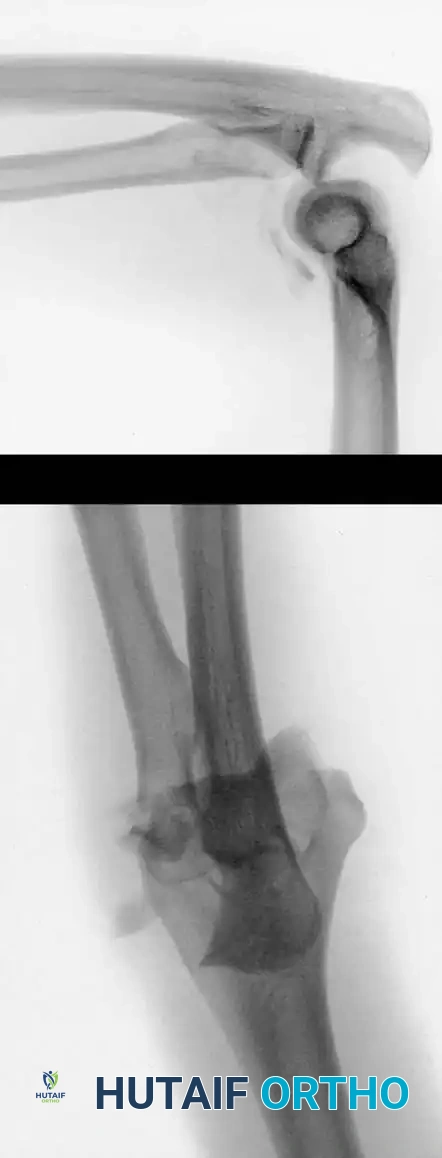

Image

Fig. 5: Intraoperative and radiographic views demonstrating robust bicolumnar parallel plating.